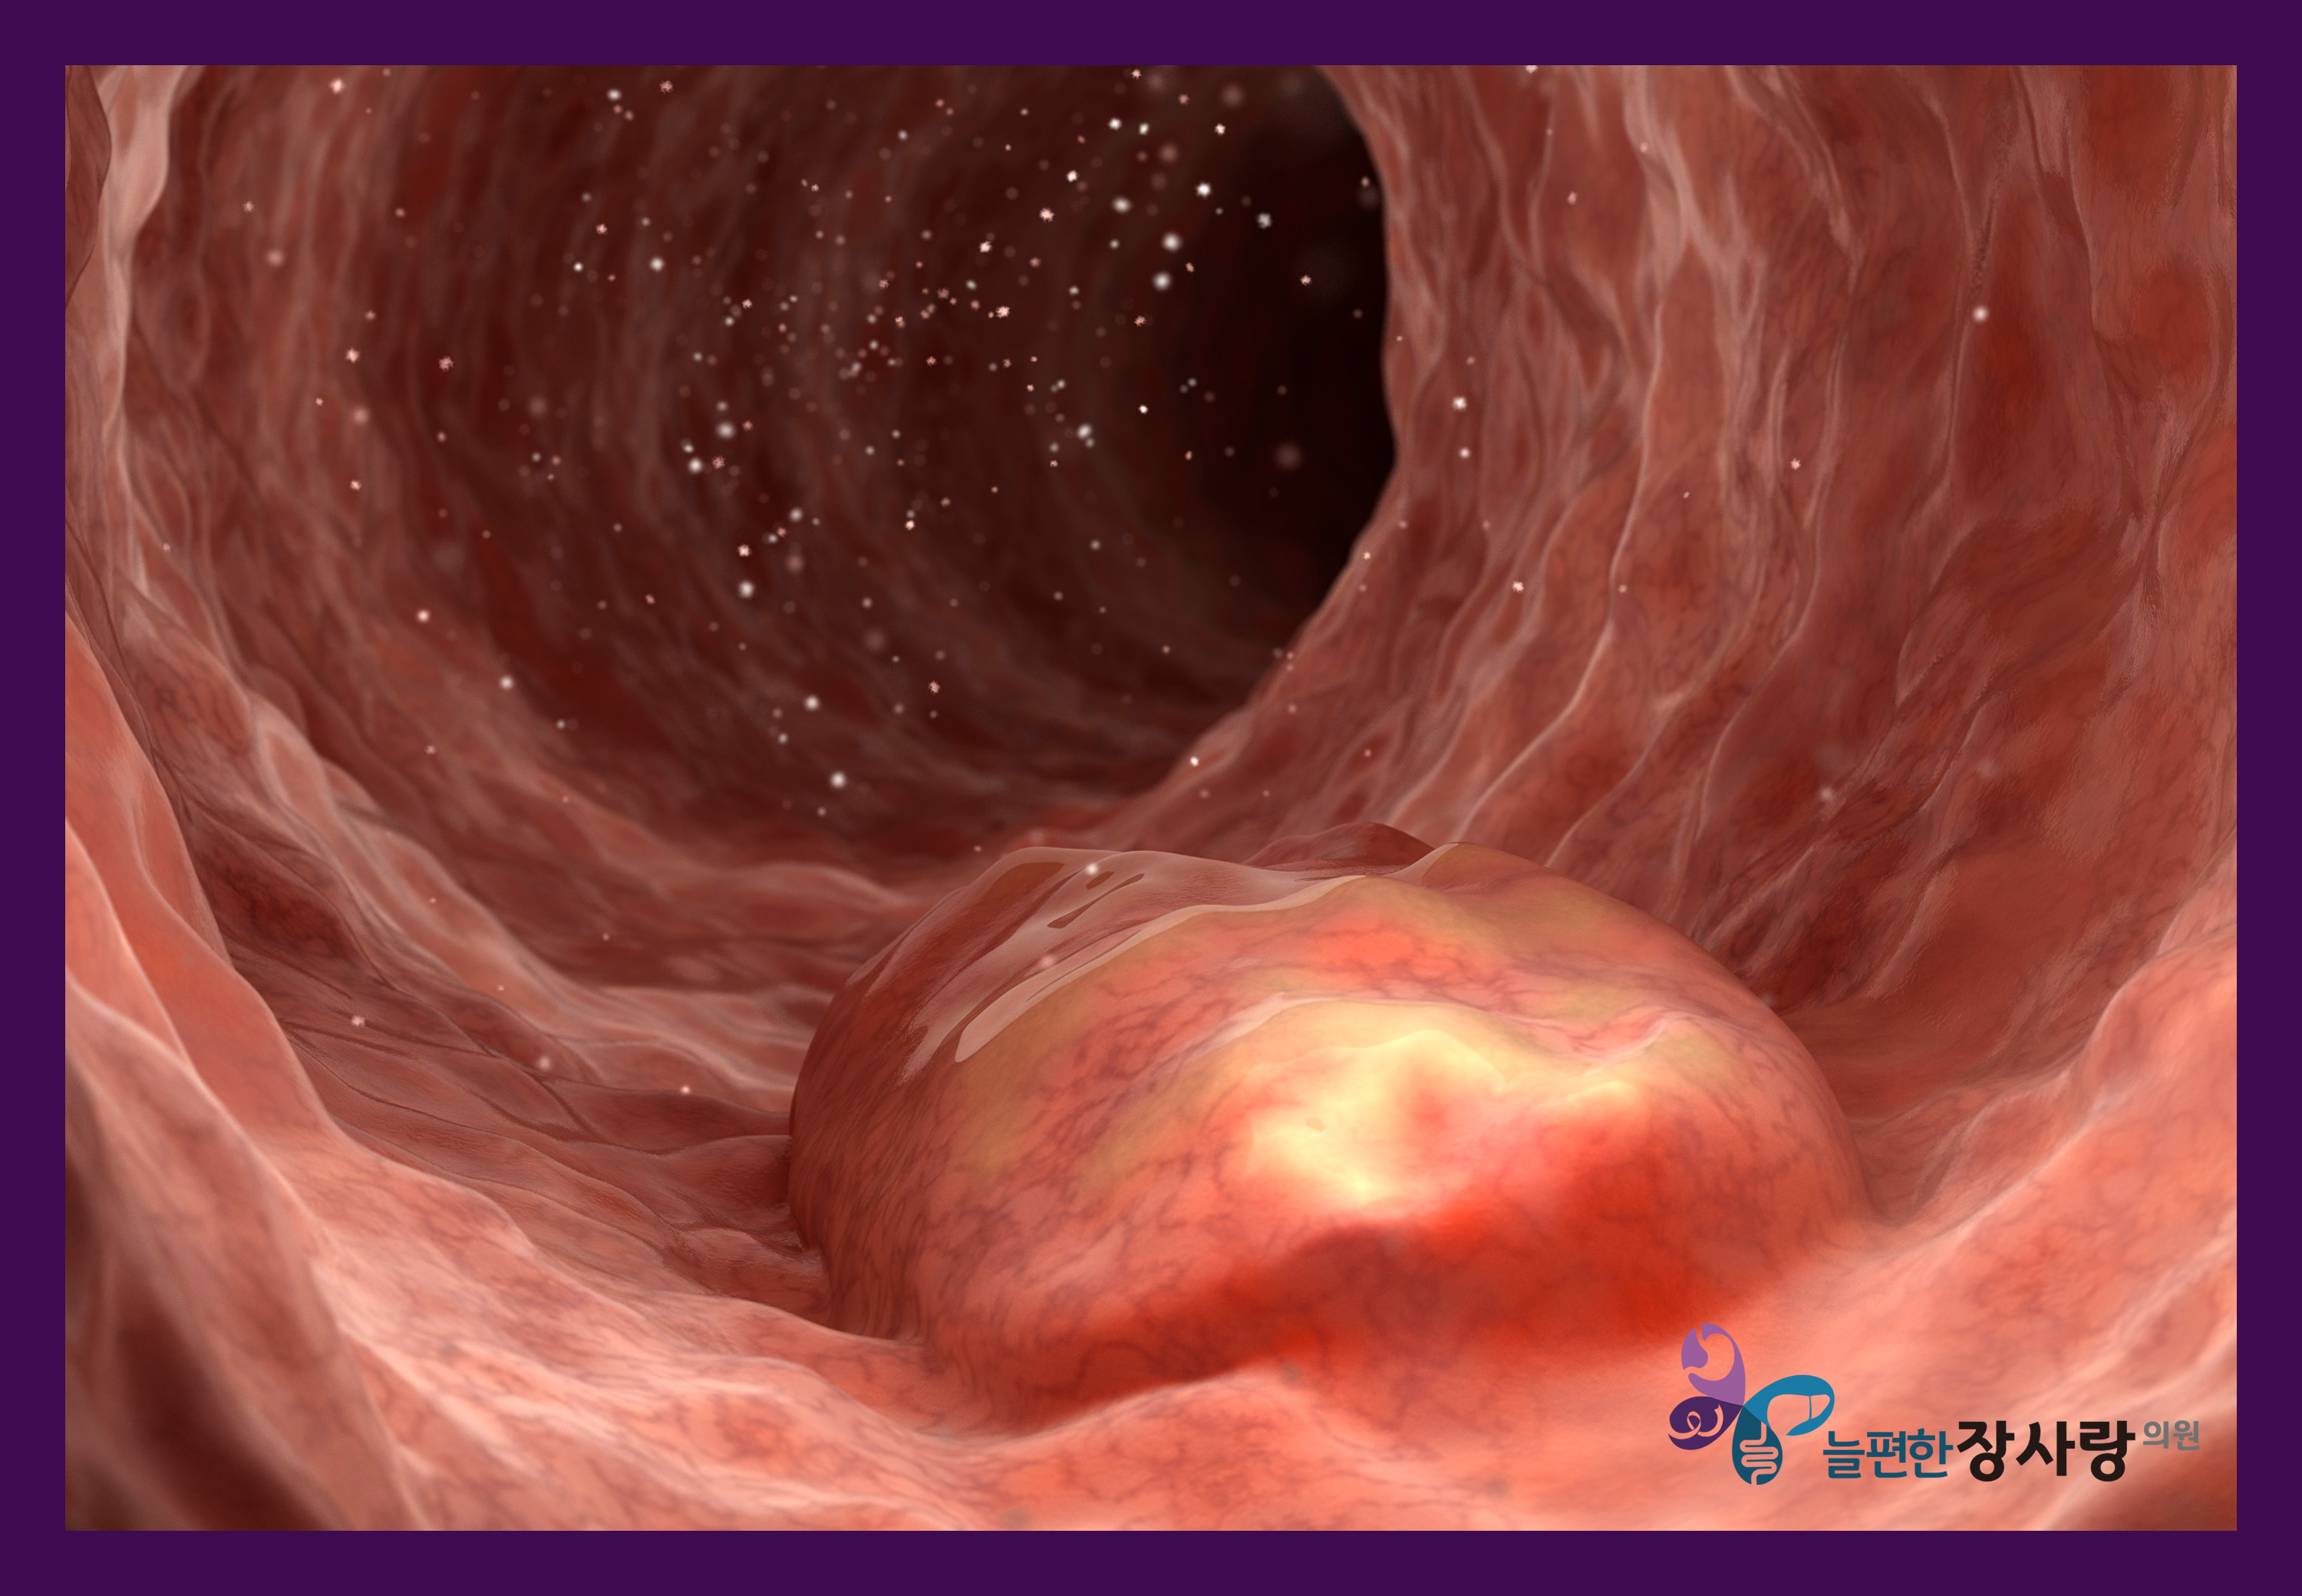

대장 용종이나 초기 대장 질환 역시

검사 과정에서 발견되는 경우가 많습니다.

대장내시경은 항문을 통해 내시경을 삽입하여

대장 내부의 염증, 용종, 종양 등을 확인하는 검사로,

대장뿐 아니라 소장 말단 부위까지 관찰이 가능합니다.

이를 통해 염증성 장 질환, 대장 용종, 대장암, 게실 질환 등

대장암은 초기 단계에서

뚜렷한 증상이 나타나지 않는 경우가 많습니다.

조기에 발견되는 병변은

내시경을 통한 치료에 도움이 됩니다.

대장내시경 중 용종이 발견될 경우에는

상황에 따라 당일 용종 절제술이 가능해

검사와 치료를 한 번에 진행할 수 있습니다.